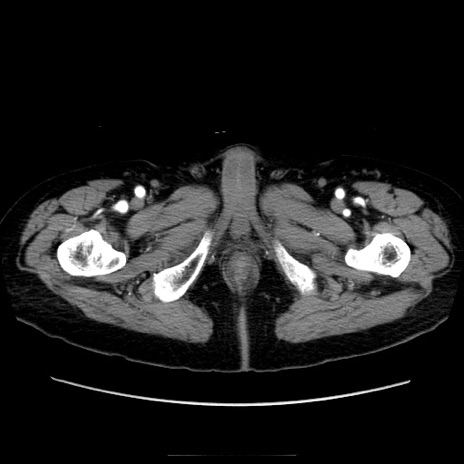

症例21(横断像)

【症例】70歳代男性

【現病歴】肝硬変・肝細胞癌にてかかりつけの方。約9時間前に食後より腹痛出現。症状が徐々に増悪し、嘔吐出現したため来院。

【既往歴】肝硬変、肝細胞癌(RFA、TACE後)

【身体所見】意識清明、表情苦悶様、BT 36℃、BP 129/78mmHg、P 88bpm、SpO2 97%(RA)、右上腹部から心窩部にかけて圧痛あり、反跳痛なし、筋性防御あり。